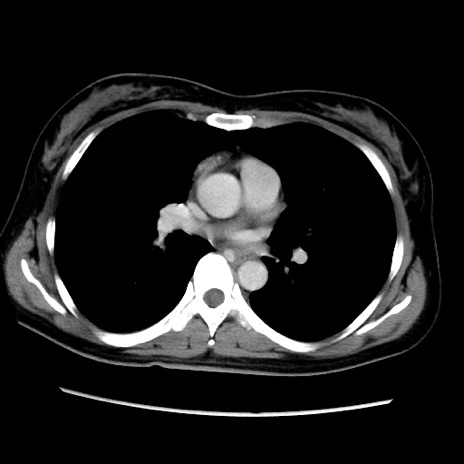

症例39(横断像)

【症例】40歳代女性

【主訴】上下腹部痛

【現病歴】2日目から下腹部痛あり。夜間は痛みで眠れなかった。昨日より上腹部痛と下痢が出現。臥位で痛みは軽快したため、休んでいた。本日になって臥位でも立位でも痛みが強くなってきたため救急要請。

【既往歴】子宮内膜症

【身体所見】部:平坦・軟、左上下腹部に圧痛あり、反跳痛あり。

【データ】WBC 21800、CRP 26.78